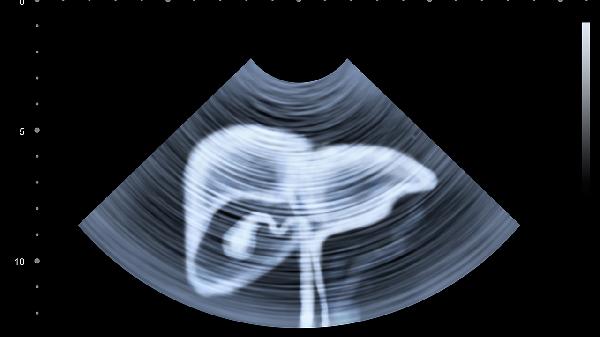

一、脂肪肝到肝癌的演变过程

1、单纯性脂肪肝阶段

肝脏刚开始堆积脂肪,肝功能基本正常。这个阶段完全可逆,通过调整生活方式就能恢复。但大多数人因为没有症状而忽视。

2、脂肪性肝炎阶段

肝脏开始出现炎症反应,转氨酶可能轻度升高。此时及时干预仍有机会逆转,但需要更严格的治疗和监测。

3、肝纤维化阶段

持续的炎症导致肝脏组织开始"结疤",这个阶段逆转难度加大,需要专业医疗干预配合生活方式改变。

4、肝硬化阶段

肝脏结构发生不可逆改变,功能严重受损。此时癌变风险显著增加,每年约有3-5%的肝硬化患者会发展为肝癌。